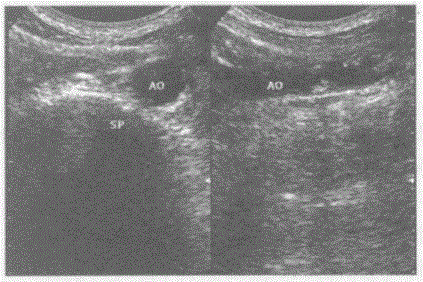

问题 临床资料:男,46岁,自述患高血压、高血脂、糖尿病,常规体检。 超声综合描述:腹主动脉内膜粗糙,连续性差,管壁回声强弱不均,可见多个大小不等强回声、中等回声光团,部分后伴声影。 超声提示:

选项 A.腹主动脉正常声像图 B.腹主动脉瘤 C.大动脉炎 D.腹主动脉粥样硬化并多发软斑、钙化斑形成

答案 D